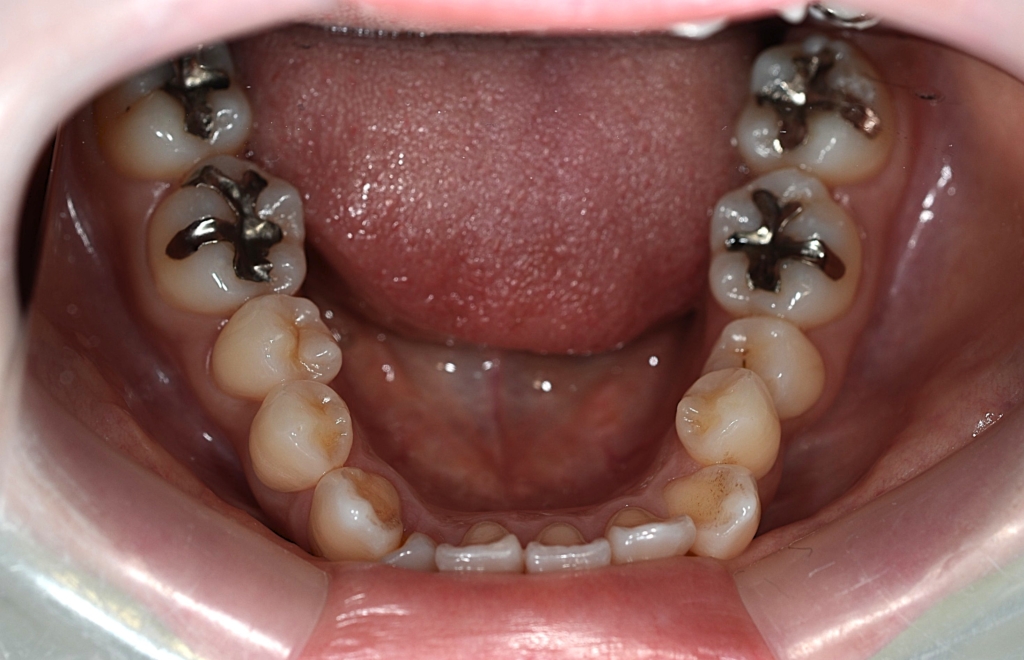

患者さんは、20代の女性(社会人)です。

「八重歯などのガタガタを治してきれいな歯並びになりたい!」

というのが一番の希望でした。

可能なら口元がちょっと引っ込めばもっと嬉しい、というものでした。

#1.顎と歯の不調和による叢生(重度)

#2.上顎前突(奥歯の噛み合わせ)

と診断しました。